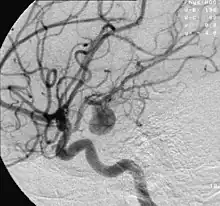

| Angiography of an aneurysm in a brain artery. The aneurysm is the large bulge in the center of the image. | |